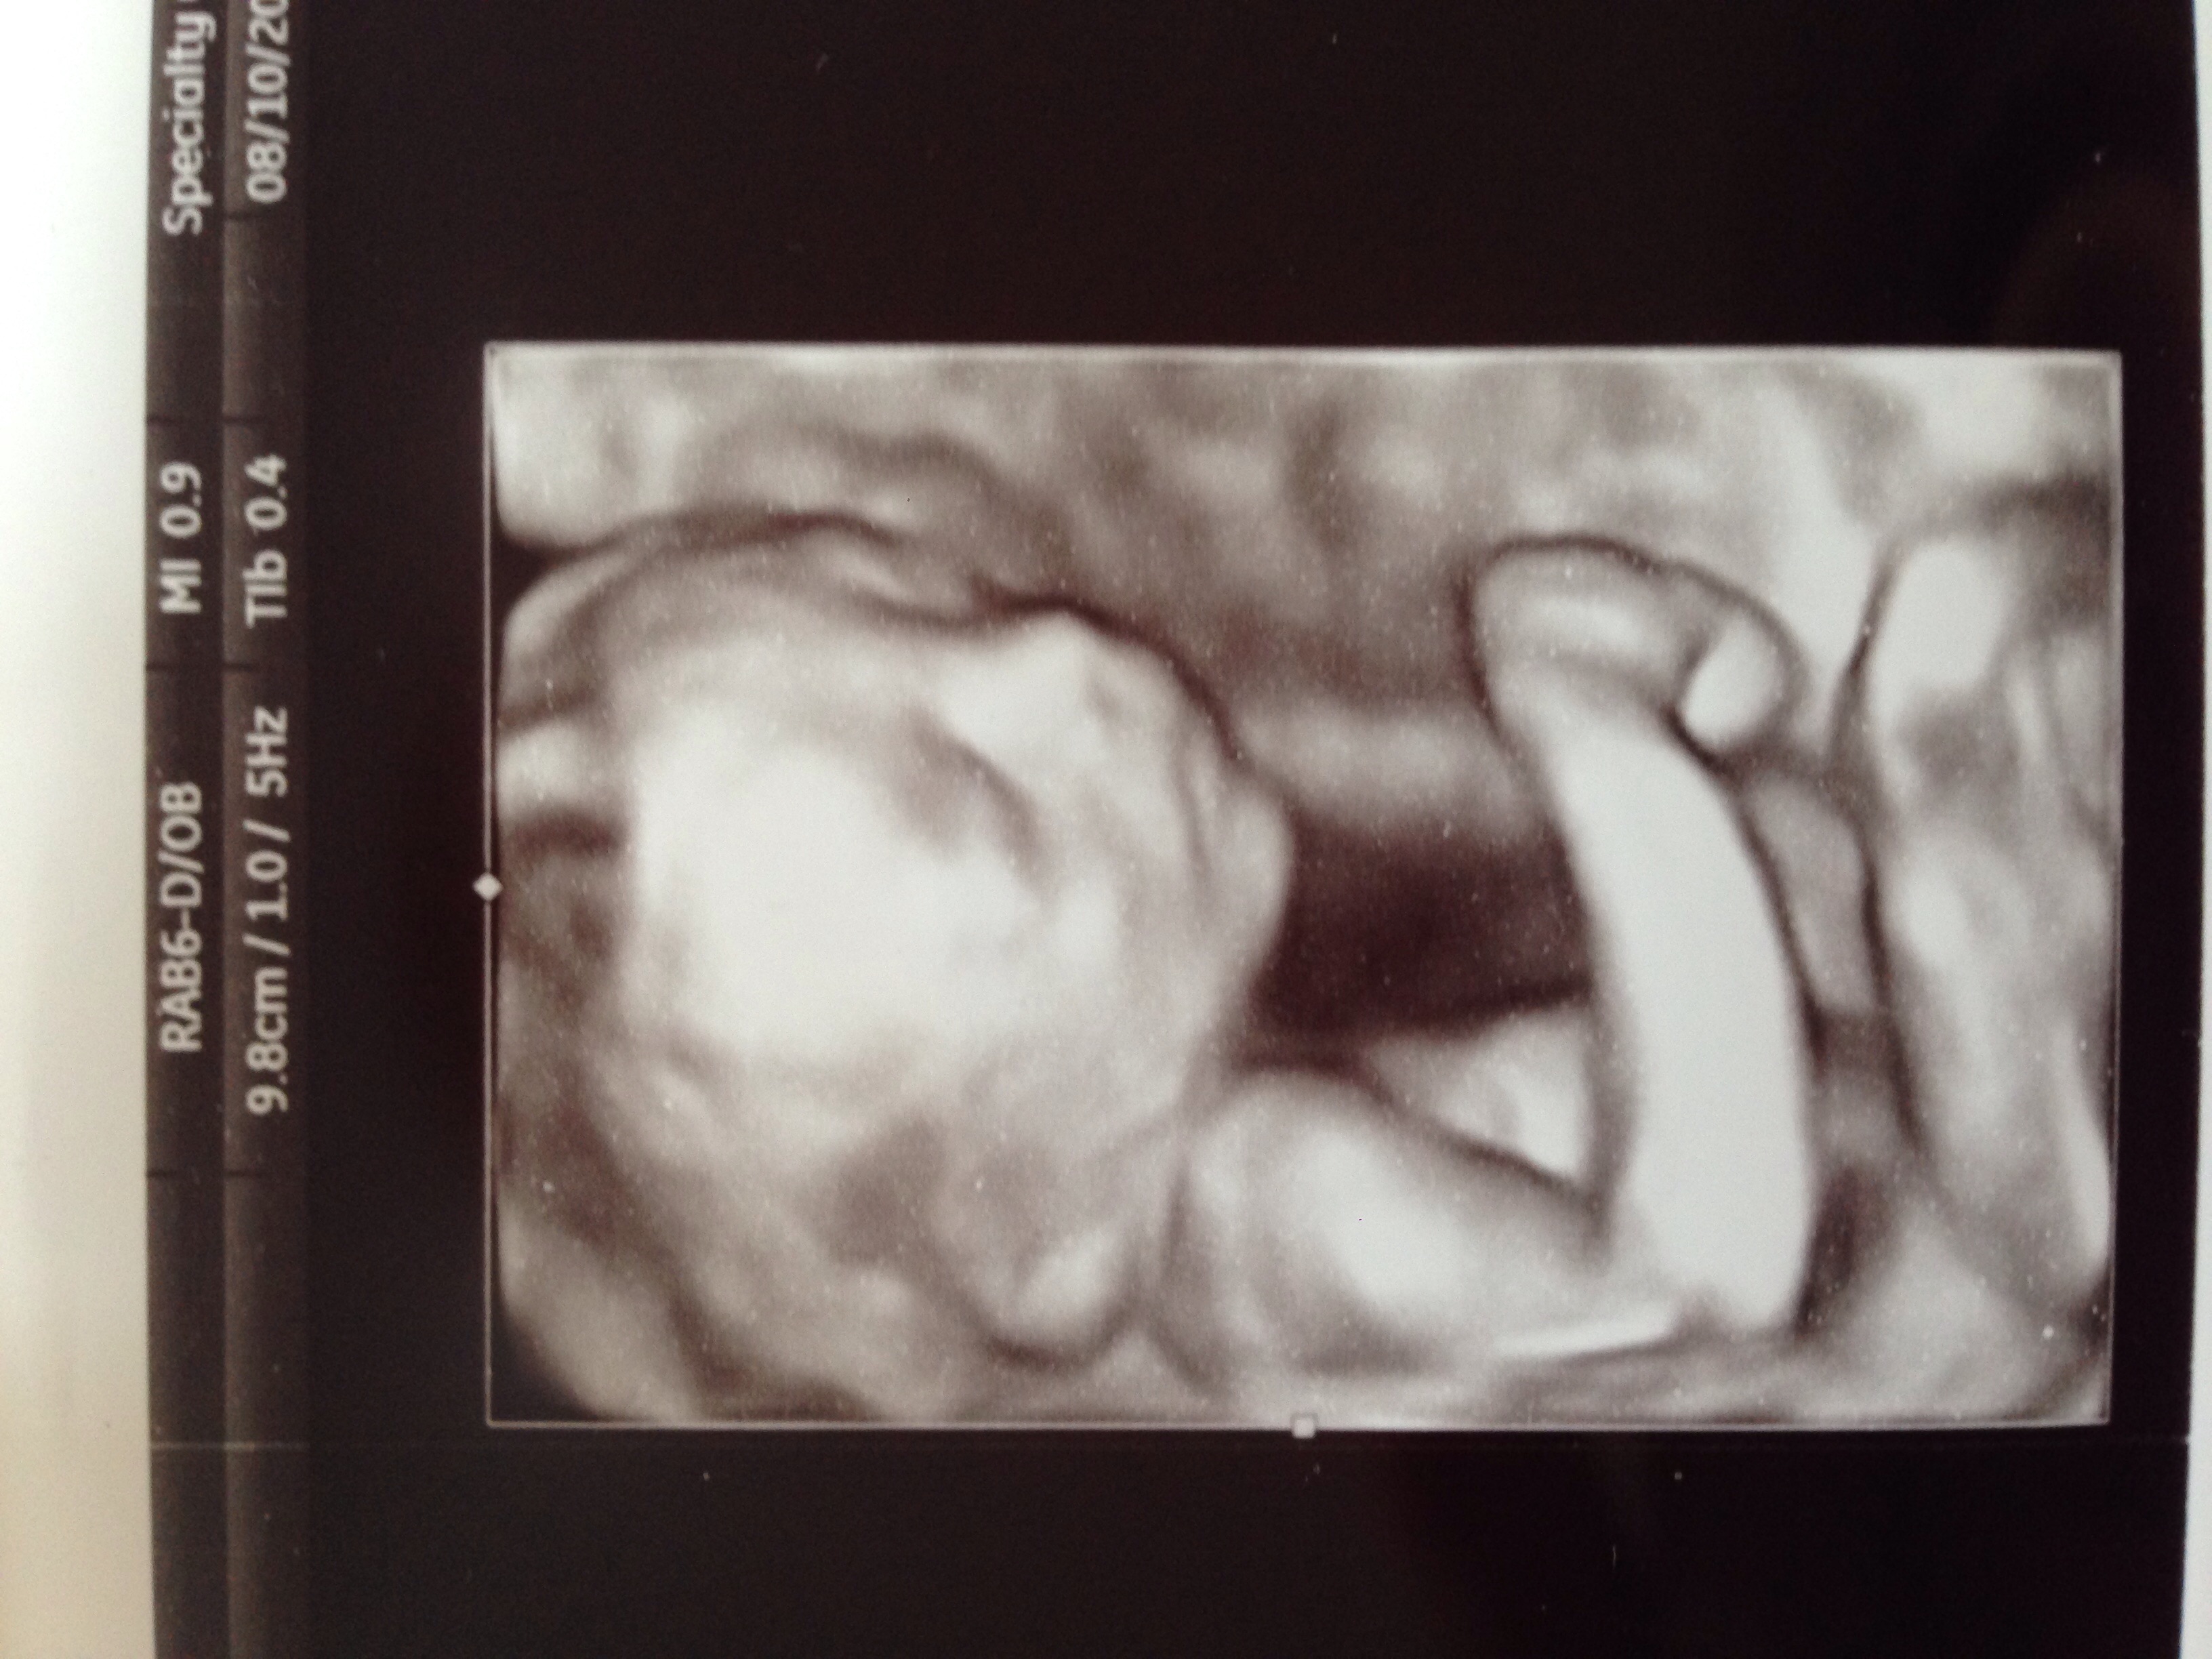

• We had our scan about a week ago, but I just realized this thread was here lol. Baby is on perfect health and we found out we're having a girl! She was kicking up a storm and we got to see her smile and wave at us. It was truly an amazing experience :\">

• I had my scan yesterday and we confirmed that she's definitely a girl, and she's definitely healthy! In fact, the doctor called her a "textbook perfect baby." Not sure how she'll ever live up to that label!

• Had my scan today at 22 weeks.. Baby girl is healthy and very active. She's perfect and we couldn't be happier or more excited!

• This morning I confirmed my feeling that I'm having a girl!! :\">